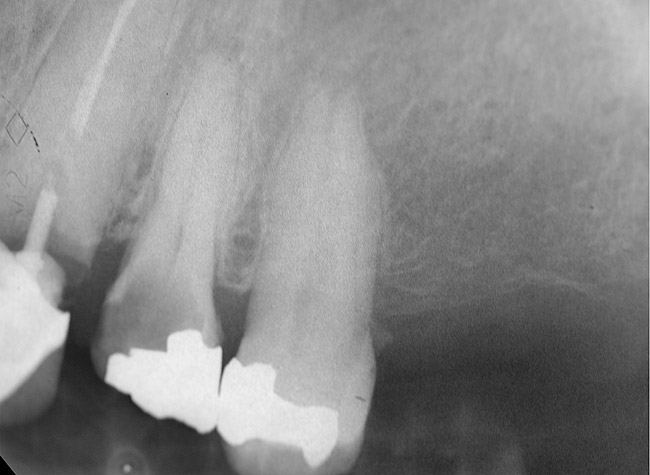

Figure 7  Condition of the teeth seen in Figure 6, approximately 5 years after restoration. Note the extensive furcation involvement of tooth No. 31 and its residual periapical radiolucency.

Figure 7

Figure 8  Same case as in Figure 7 showing teeth Nos. 28 and 29. Note that tooth No. 28 was included into the four-unit restoration, and the small radiolucency on the distal tooth No. 29, which was associated with a root fracture.

Figure 8

The clinician also must consider the status of the adjacent teeth. Figure 6 shows teeth Nos. 29 and 31 prepared for a fixed bridge. Factors to be considered in this example were the short root of tooth No. 29 with a distal biologic width violation and a short root trunk on tooth No. 31 (which leads to furcation involvement with a small amount of facial or lingual bone loss). This patient also had periodontal disease, which further decreased the long-term prognosis of the fixed bridge option. No prospective studies directly compare the longevity of the two options: a three-unit fixed bridge vs an implant.37 Other factors that complicate comparisons of an implant vs a fixed three-unit bridge are the variability of fixed bridges as well as the variability of the implants (amount of bone, implant length, etc). For example, endodontically treated abutment teeth do not last as long as nonendodontically treated abutment teeth.38 Restorations on teeth with endodontic posts and a minimal length of ferrule do not persist as long as those on teeth without a post and at least a 2-mm ferrule.39

In this example, the more predictable option would have been to place an implant in the No. 30 position and restore the area as three single units. However, the treatment delivered involved a four-unit fixed bridge, which then included tooth No. 28. Unfortunately, this bridge failed at approximately 5 years (Figure 7 and Figure 8) because of a root fracture of tooth No. 29 and advanced furcation involvement with residual endodontic infection of tooth No. 30. The inclusion of tooth No. 28 into the bridge also decreased its long-term prognosis because of its preparation.43 The alternative restorative option of a RPD also would decrease the prognosis of the RPD abutment teeth, which fail more often than FPD abutment teeth.43